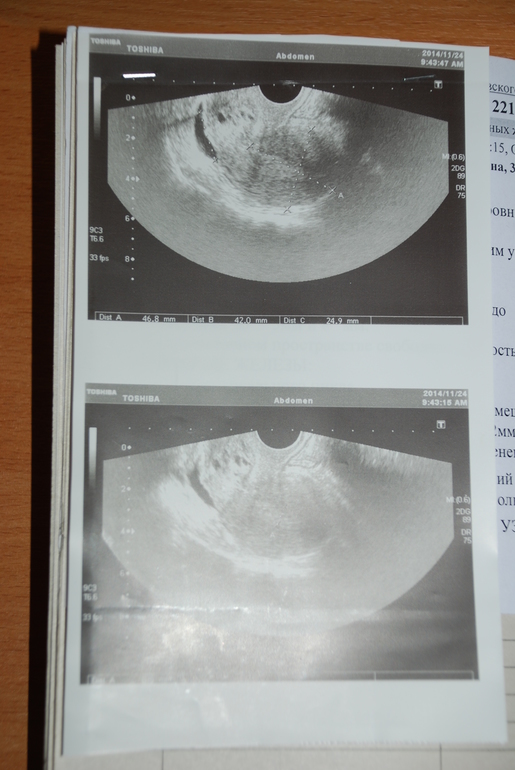

вот это самое первое, осень 2014:

Ну сокрее всего гиперплазия! !!!это все прекрасно решает гистера